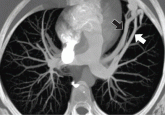

ArticleWhen does chest CT require contrast enhancement?Author:Rahul Renapurkar, MDPublish date: June 1, 2016It may be needed in cases of suspected cancer or thoracovascular diseaseRead More